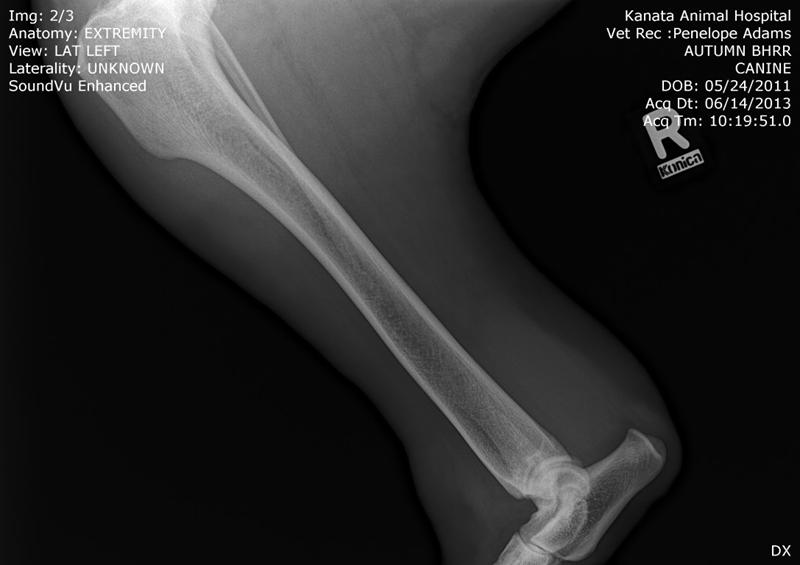

Below are two of her x-rays taken on June 14th, 2013